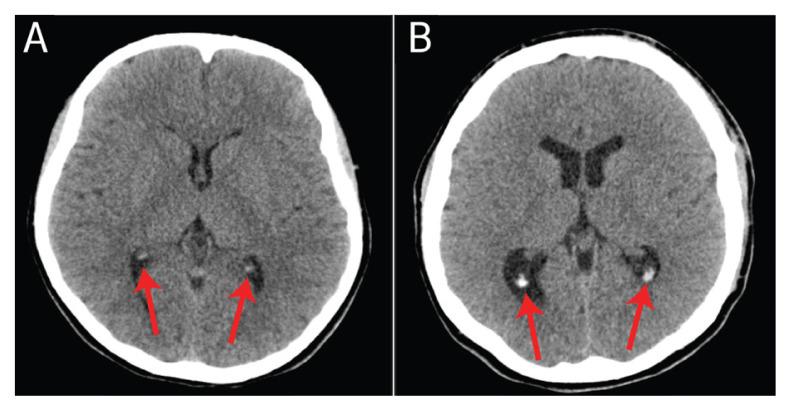

A total of 460 patients were examined, with a mean age of 6.54 ± 4.94 years. The frequency of PIC in boys and girls was 35.1% and 35.4%, respectively. PICs were most common in choroid plexus, observed in 35.2% (age range: 0.4-15 years, median: 12 years) of subjects, followed by the pineal gland in 21.1% (age range: 0.5-15 years, median: 12 years) and the habenular nucleus in 13.0% of subjects (age range: 2.9-15 years; median: 12 years). PICs were less common in falx cerebri, observed in 5.9% (age range: 2.8-15 years; median: 13 years) of subjects, and tentorium cerebelli, observed in 3.0% (age range: 7-15 years, median: 14 years) of subjects. PICs increased significantly with increase in age ( <0.001).

Choroid plexus is the most frequent site of calcification. Choroid plexus and pineal gland calcifications may be present in infants younger than one year. Recognising PICs is clinically important for radiologists as they can be mistaken for haemorrhage or pathological entities such as neoplasms or metabolic diseases.

共检查了 460 例患者,平均年龄为 6.54±4.94 岁。男孩和女孩 PIC 的发生率分别为 35.1%和 35.4%。脉络丛是 PIC 最常见的部位,在 35.2%(年龄范围:0.4-15 岁,中位数:12 岁)的患者中观察到,其次是松果体在 21.1%(年龄范围:0.5-15 岁,中位数:12 岁)和缰核在 13.0%(年龄范围:2.9-15 岁;中位数:12 岁)的患者中。大脑镰钙化较少见,见于 5.9%(年龄范围:2.8-15 岁;中位数:13 岁)的患者,小脑幕钙化见于 3.0%(年龄范围:7-15 岁,中位数:14 岁)的患者。PIC 随着年龄的增加而显著增加(<0.001)。

脉络丛是最常见的钙化部位。脉络丛和松果体钙化可能出现在一岁以下的婴儿中。放射科医生认识到 PIC 很重要,因为它们可能被误诊为出血或肿瘤或代谢疾病等病理性实体。